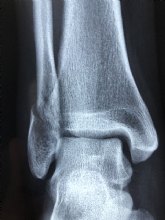

En el caso de que el esguince sea leve –grado I-, se manifiesta con dolor, hinchazón leve y, en algunas ocasiones, un ligero moratón, pero no se pierde movilidad en el tobillo y la persona es capaz de caminar, ya que el ligamento solo se ha estirado demasiado o roto ligeramente (menos del 5% de las fibras). Si hay un desgarro o rotura parcial del ligamento -grado II-, aumentan el dolor, la inflamación, el hematoma puede ser mayor y la movilidad del tobillo puede verse limitada. También puede resultar difícil apoyar peso sobre el pie, lo que resulta imposible en caso de esguince severo -de grado III-, consecuencia de una rotura o desgarro total del ligamento (que cursa además con gran inflamación y hematoma muy evidente).